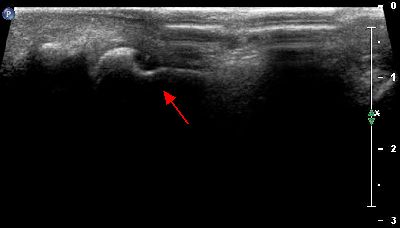

Becco osteofitico della 1a articolazione metatarso-falangea becco osteofitico prima metatarso-falangea